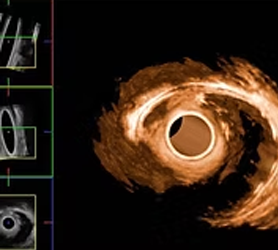

ultrasonidoUltrasonido endoanal 3D y endorrectal 360º

Estudios indispensables para identificar lesiones y etapificar oportunamente tumores malignos de recto.